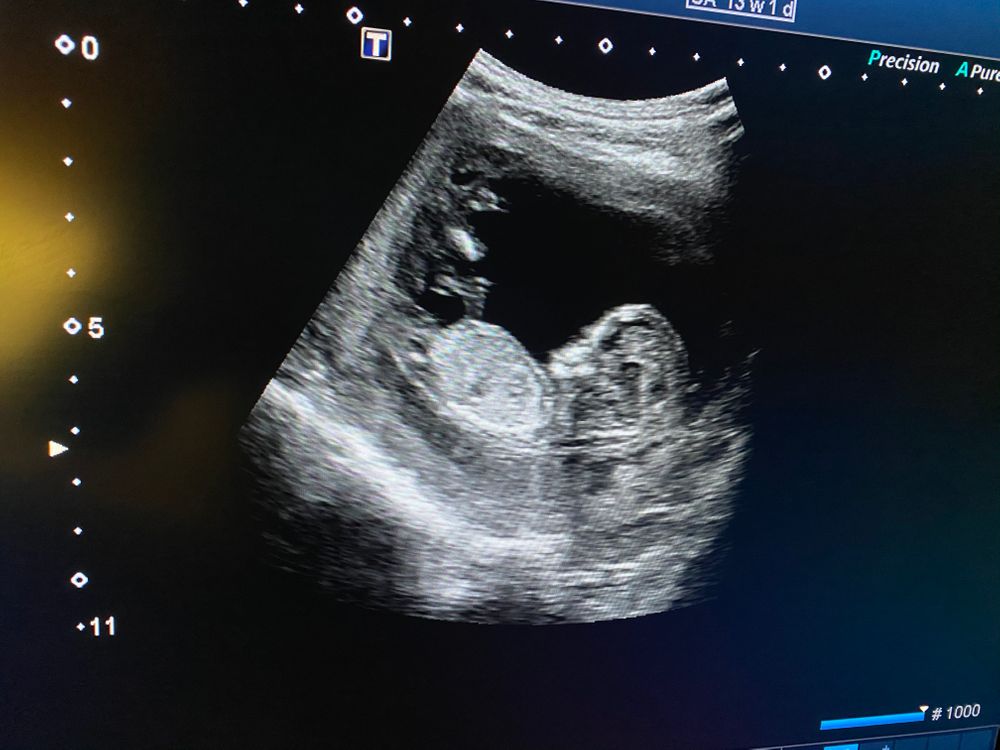

Всем привет! Вчера была на скрининге, врач сказала, что: «немного расширено воротниковое пространство, но как едиенственное небольшое отклонение от норм -это не показатель». Что в остальном развивается по сроку и что будет видна общая картина после результатов крови. Ну и естественно в случае выявления рисков по крови мне сообщат в течении трёх дней. Я конечно на панике, хоть ее слова о том,что отдельно это не показатель, меня и немного успокоили... Кто с таким сталкивался, все ли у вас хорошо? Результаты будут я думаю не раньше среды и то в ЖК придётся звонить или ехать 😓

Вот пока не знаю, тк результатов пока нет. Могу попробовать снимок узи прикрепить, но там мне кажется ничего не видно...